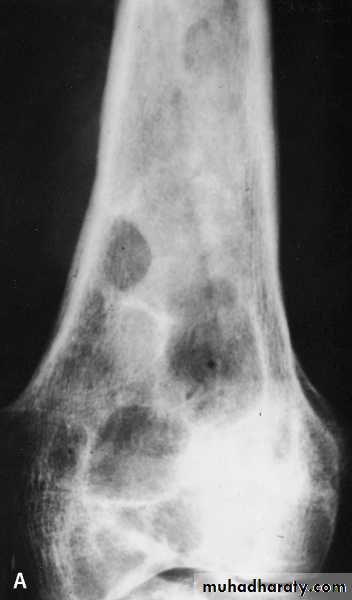

osseous H. cyst

When the embryo of E. granulosus reaches bony tissues it will develop to osseous hydatid cyst.It is occur in the ends of long bones and pelvic arch

sterile never produces brood capsule and protoscolices with little or no fluid and no fibrous capsule.

• X-ray picture: useful to detect the calcified cyst.